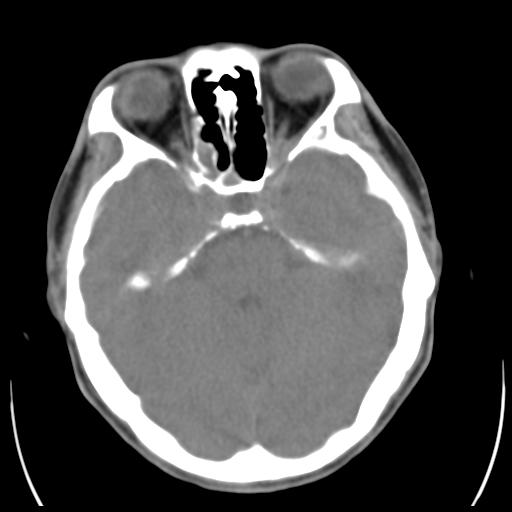

35m 鼻子时不时流血,头及右侧面部痛,颈部淋巴结未见明显大

这个东西大家仔细看看呀

考虑鼻咽癌侵犯颅底并突入右侧鼻腔;双侧中耳乳突炎。

蝶窦,后组筛窦及鼻咽部团块状软组织影,骨壁破坏,病变较广泛。考虑恶性肉芽肿。建议活检。

考虑中线肉芽肿(鼻硬结病),次之tb或真菌感染性肉芽肿,病变形态不像肿瘤,建议增强及活检。

蝶窦,后组筛窦及鼻咽部团块状软组织影,骨壁破坏,病变较广泛。考虑炎性肉芽肿性病变可能。建议活检。